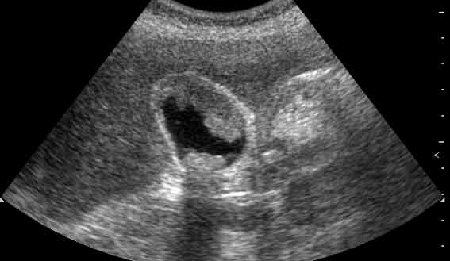

УЗИ: опухоль и конкременты желчного пузыря

Опухоль передней стенки и конкременты желчного пузыря.

Tags: Tumor the anterior wall and of the gallbladder, stones.